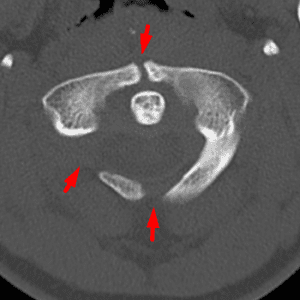

Congenital Anomalies of C1

Mimicking a fracture